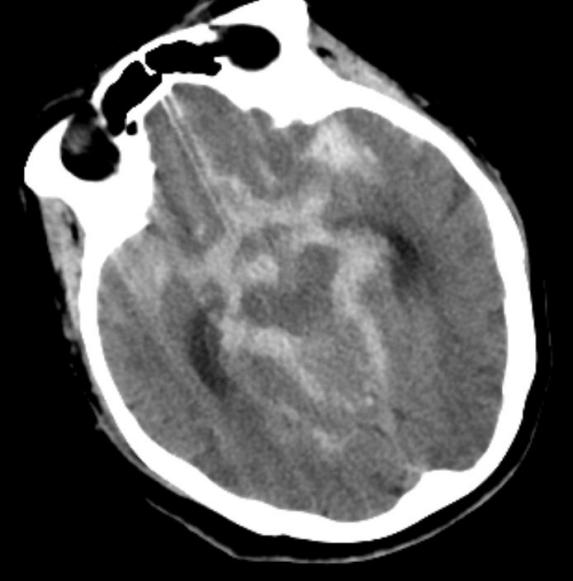

赵女士今年已85岁高龄,患高血压病已30余年,冠心病10余年,曾置入5枚冠状动脉支架,平时可自理。7月8日晚间在家中洗澡时突发剧烈头痛,伴恶心呕吐,紧急来到北京市垂杨柳医院急诊内科就诊。经为患者行头颅CT检查提示蛛网膜下腔出血,急诊当即请神经外科会诊。神经外科值班医生刘耀东赶到急诊,查看患者呈嗜睡状态,颈项强直。紧急为患者安排了头颈动脉CTA检查,显示前交通动脉瘤。

头颅CT显示广泛蛛网膜下腔出血,脑室积血